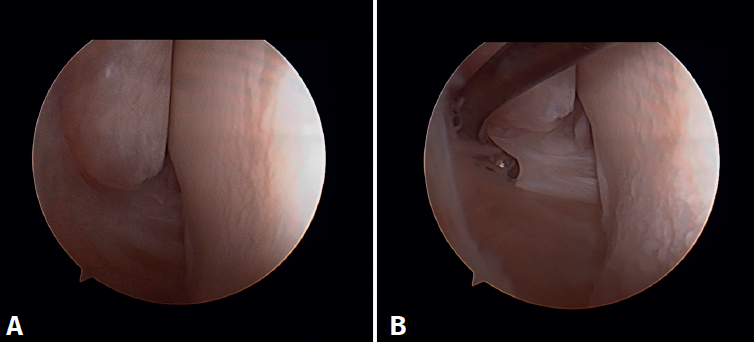

Arthroscopic evaluation of the syndesmosis

From the anteromedial portal we can directly visualize the distal fibers of the ATFL. Disinsertion of these fibers does not always result in instability of the syndesmosis, but it does require us to check it. In our experience, we prefer assessment of the coronal plane of the syndesmosis. We introduce the arthroscope into the tibiotalar joint directing the camera cranially. In this way we have a direct view of the distal tibiofibular joint. We then assess stability by attempting to insert the palpation probe into the joint. If it is possible to do so, we classify the syndesmosis injury as unstable (Figure 6A).

Arthroscopic evaluation of the deltoid ligament

There are multiple methods for assessing instability of the medial complex; using the anterior ankle portals it is possible to assess the stability of the deltoid ligament in its main plane of action, corresponding to the coronal plane. Chun et al.(20) described instability when it is possible to introduce an arthroscopic palpation probe into the medial tibiotalar space (Figure 6B). Vega et al.(21) reported that, in the majority of injuries, the most anterior portion of the deltoid ligament is detached from the medial malleolus, while its proximal insertions remain intact. In this situation, the arthroscopic palpation probe can be inserted between the medial wall of the internal malleolus and the deep fibers of the deltoid ligament.